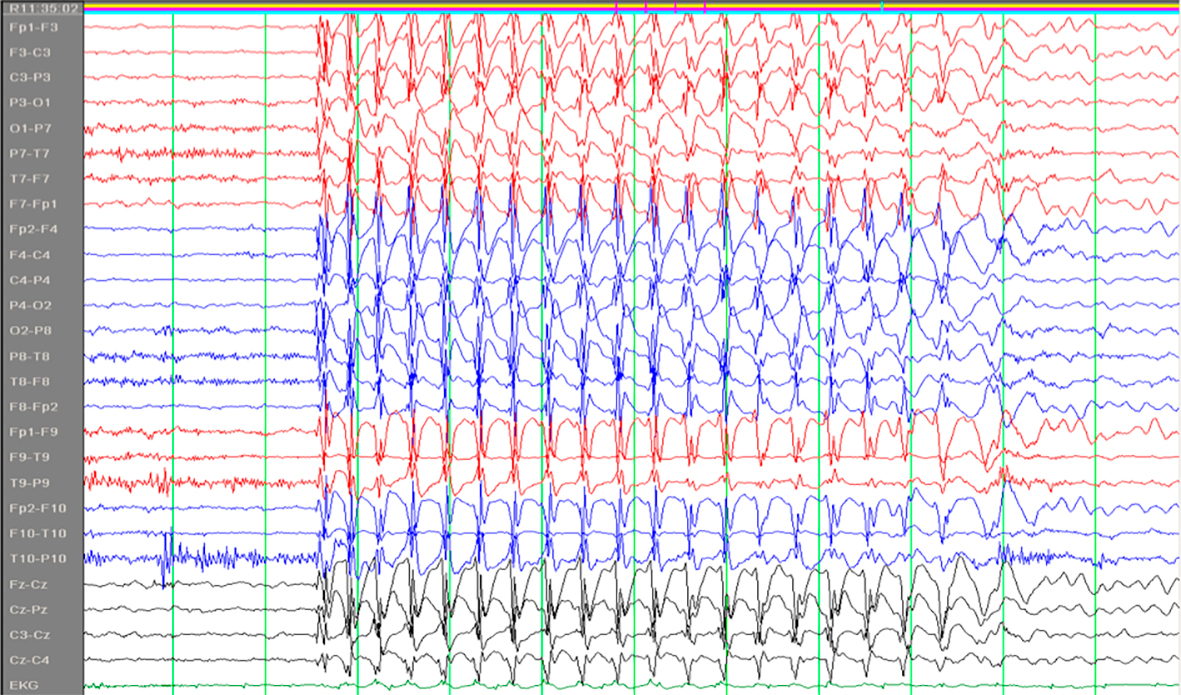

Absenser er en type epileptiske anfall som kan ses ved flere generaliserte epilepsiformer, først og fremst ved absensepilepsi i barnealderen. Ordet stammer fra det franske absence og det latinske absentia og kan oversettes med åndsfravær. Barna blir i noen sekunder fraværende i sin virksomhet eller tale, uten at vedkommende selv merker det. De får et tomt, stirrende blikk. Det er ingen kramper, men av og til ses diskrete rykninger i øyelokkene. Det er viktig at foreldre er oppmerksomme på slike tilfeller hos barn. Absensene har et spesifikt EEG-korrelat; 3/sekund «spike-waves» (fig 1) (1).

Absensbegrepet bør reserveres til den spesifikke anfallsformen som er nevnt over, og som er ledsaget av nevnte EEG-korrelat. Er man som kliniker usikker på hva slags anfall pasienten har, bør man heller beskrive anfallet med ord som episoder med fjernhet, manglende kontakt, redusert bevissthet e.l.